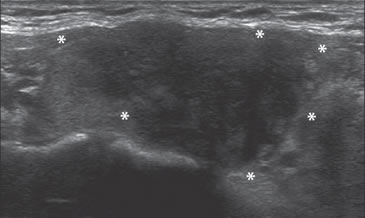

Figura 31. Área hipoecogénica en el lóbulo tiroideo aumentado de

volumen (asteriscos) que corresponde a un foco de tiroiditis de De

Quervain, que simula un tumor maligno.

La tiroiditis subaguda de De Quervain, inhabitualmente puede producir un área hipoecogénica que se confunde con una forma infiltrativa de cáncer papilar (Figura 31b), especialmente si no es dolorosa a la palpación y no hay sospecha clínica. Hay algunas lesiones benignas que también pueden mostrar un patrón similar al descrito, pero la mayor parte de las veces son marcadamente hipovascularizadas, a diferencia de la tiroiditis subaguda y el cáncer papilar (Figura 31b) que muestran vasos en la lesión.